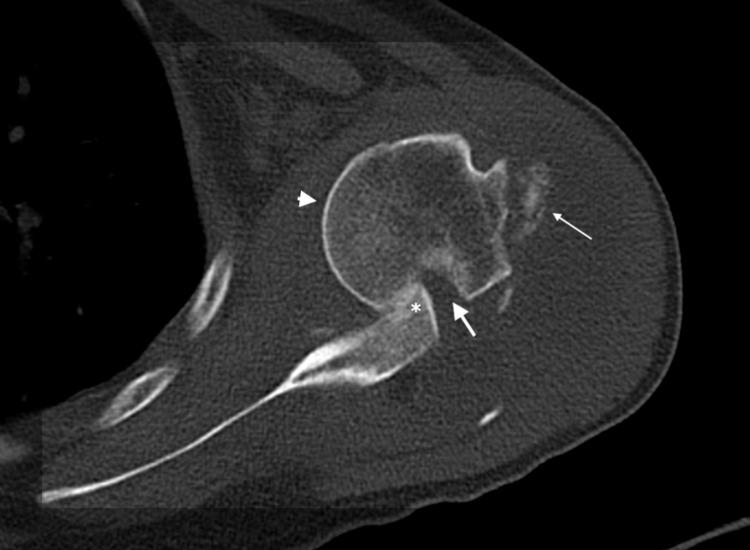

陈旧性肩关节前脱位伴锁扣征的治疗:两例报告

Management of Neglected Locked Anterior Dislocation of Shoulder: A Report of Two Cases.

There is a paucity of literature regarding a neglected shoulder dislocation, as it is unusual to miss it clinically due to the apparent deformity. Nevertheless, in some cases, particularly those who received the primary treatment from a local bonesetter, present with neglected dislocation. No high-level studies comparing different treatment modalities in such a situation are available. Therefore, most of the treatment recommendations are based on level four studies and the literature for recurrent dislocation of the shoulder. We herewith describe two cases of neglected anterior dislocation of the shoulder, which we have managed by open reduction and Latarjet procedure in one and Bankart surgery in the other patient. Both of our patients after one-year follow-up had a painless joint with improved yet limited range of motion. This case discussion helps in learning the approach towards the treatment of these patients. It also suggests a sub-optimal functional outcome in them.

关于被忽视的肩关节脱位的文献较少,因为临床上因明显畸形而漏诊这种情况并不常见。然而,在某些情况下,特别是那些最初由当地接骨师治疗的患者,会出现被忽视的脱位。目前尚无在这种情况下比较不同治疗方式的高水平研究。因此,大多数治疗建议基于四级研究以及关于复发性肩关节脱位的文献。我们在此描述两例被忽视的肩关节前脱位病例,其中一例我们采用切开复位和Latarjet手术治疗,另一例患者采用Bankart手术治疗。我们的两名患者在随访一年后关节无痛,活动范围有所改善但仍有限。该病例讨论有助于了解这些患者的治疗方法。这也表明他们的功能结果欠佳。